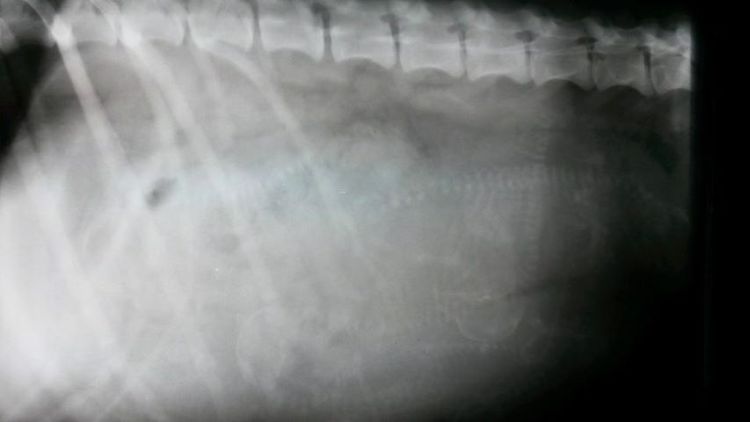

- ELDOR - Wir waren mit Eldor in der Tierklinik in Hofheim. Dort wurde er gründlich untersucht, geröngt und endoskopisch unter die Lupe genommen. FAKT: Eldor hat eine Rechtsaorta. Im April soll dies nun operativ korrigiert werden. Genaueres nach der OP ... Extraseite: "Eldor" |

Röntgentermin beim Tierarztteam Jörn Emmerich in Vallendar 08. Januar 2014 Also ... gestern war es soweit und wir haben ein gaaaanz spezielles Bild von Keks geschossen. Zuerst war ich zwar etwas irritiert, dass das Bild mit Keks allein (ohne mich) gemacht wurde, aber der Maus ging es die ganze Zeit sehr gut und sie war auch ganz brav!!! Nach dem Bild durfte ich zur Besprechung rein. Herr Emmerich ist von Keks´ körperlichem und gesundheitlichen Zustand begeistert und er sieht keinerlei Probleme auf uns zukommen. Nichts desto trotz stehen er und Frau Dr. Häberlein nun auf Abruf bereit. ![]() Wer nun möchte, kann ja mal versuchen, die kleinen Kekskrümelchen zu zählen. Ich gebe einen Tipp: Es sind mehr als 6, aber weniger als 10. :-) Bisher ist Keks noch total entspannt, auch wenn wir am Samstag einen Fehlalarm hatten (Ihre Temperatur war schon auf 37,3 Grad). Nun wird fleißig jeden Tag Fieber gemessen und ein Protokoll geführt. Seit 2 Tagen schläft Keks in der "Keksdose" (davor in meinem Bett) und ich seit Samstag davor. Sie ist noch sehr ruhig, anhänglich und hat einen Bauch mit Beulenbildung :-) Die kleinen Kekskrümelchen kann sogar jetzt jeder sehen, der einfach Keks´Bäuchlein mal länger anschaut. Ich sage immer: Die Handballmannschaft übt das prellen :-) Da kommen auch die Gefühle der eigenen Schwangerschaft wieder hoch, wenn wir so zusammen liegen und die kleinen Krümelchen in meiner Hand sich drehen und wenden oder schon das Laufen üben ... einfach unbeschreiblich! Morgen kommen Babs, Rolf und Mini. Gästezimmer ist vorbereitet (seit Samstag :-)) und dann kann es bei Keks losgehen. Sobald wir Bilder und Info´s über die kleinen Kekskrümelchen haben, dann könnt Ihr das hier nachlesen - schneller über Facebook (wird öffentllich sein). Bis dahin bitte DAUMEN drücken! |